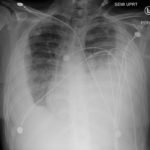

Upright frontal radiograph of the chest demonstrated large pleural effusion on the left and moderate pleural effusion on the right as shown by the visible menisci on both sides (red arrows) with diffuse bilateral nodular densities (yellow dotted lines), consistent with septic pulmonary emboli. Computed tomography (CT) of the chest demonstrated multiple scattered lung nodules bilaterally containing internal foci of air cavitation (green dotted lines).